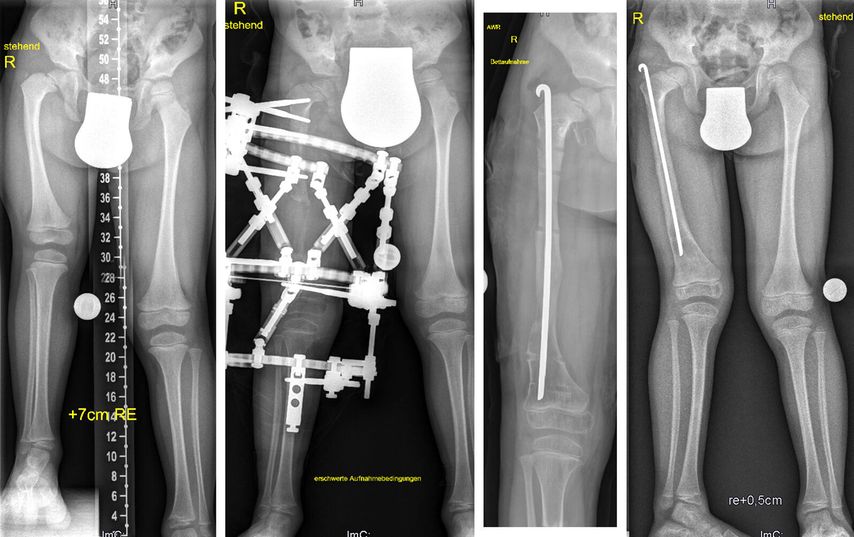

Bei Erwachsenen sind es ebenfalls erworbene und angeborene Fehlstellungen, wobei hier Pseudarthrosen (Abb. 4), infizierte Pseudarthrosen sowie nicht verheilte Arthrodesen am Fuß und Sprunggelenk hinzukommen. Bei der simplen Beinverkürzung ohne oder mit geringer Achsabweichung hat der Verlängerungsmarknagel (Precice®, Nuvasive Inc.) den externen Fixateur abgelöst. Dieser Verlängerungsmarknagel kann über einen antegraden Zugang am Oberschenkel ab dem 8.–10. Lebensjahr verwendet werden und über einen femoralen retrograden Zugang oder nach Fugenschluss an der Tibia eingesetzt werden.

Abb. 4: Dieser 42-jährige Patient erlitt eine offene Unterschenkelfraktur, die sich trotz initialen Fixateurs externe infizierte. Es erfolgten eine Lappenplastik und schließlich eine Osteosynthese mit Marknagelung. Bei der Vorstellung 4 Jahre nach dem initialen Trauma zeigten sich eine Varusfehlstellung und eine Beinverkürzung von 1,7 cm. Der Nagel wurde entfernt und eine Osteotomie proximal der ehemaligen Fraktur durchgeführt. Auch in diesem Fall wurde nach Apparatabbau ein Rush-Pin zur weiteren Stabilisierung eingebracht. Die Beinlänge und Beinachse konnten vollständig korrigiert werden